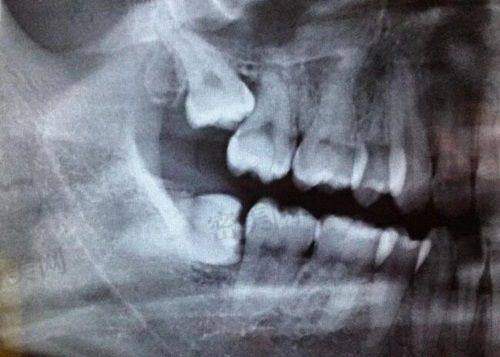

口腔 CT 设备:它能够清晰地显示口腔内部的结构,包括牙齿、颌骨、神经等。医生可以通过 CT 图像,全方面了解患者的口腔情况,为制定治疗方案提供正确的依据。与传统的 X 光片相比,口腔 CT 图像更加清晰、正确,能够发现一些细微的病变和问题。